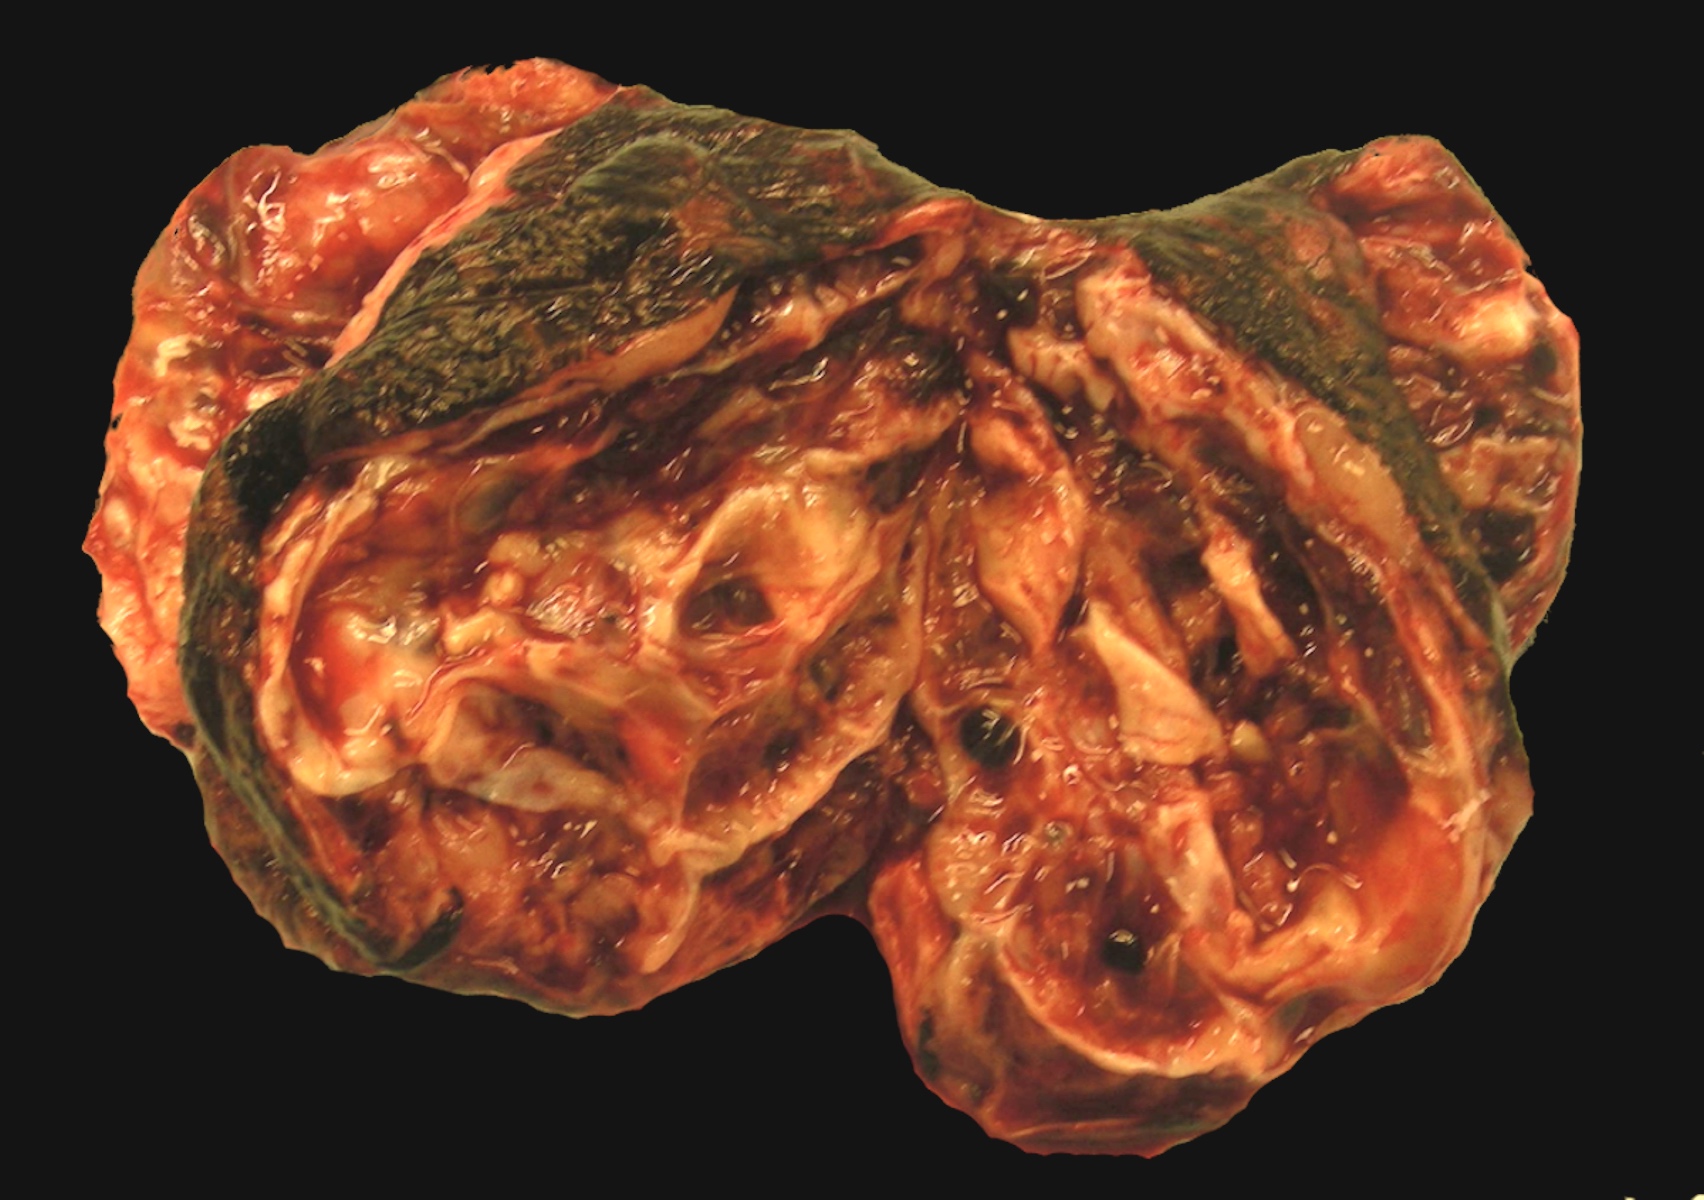

Gross description

- > 95% unilateral and confined to the ovary

- Variable size, average 10 - 12 cm

- Encapsulated with smooth lobulated surface, tan or yellow (depending on the degree of luteinization and lipid content), soft to firm (depending on the amount of fibromatous component), usually solid and cystic with straw colored or mucoid fluid, can have areas of necrosis and hemorrhage

- The more luteinized tumors are more yellow / orange

- May resemble serous cystadenoma

- Rare androgenic tumors tend to be large with thin walled cysts (Arch Pathol Lab Med 1984;108:786)